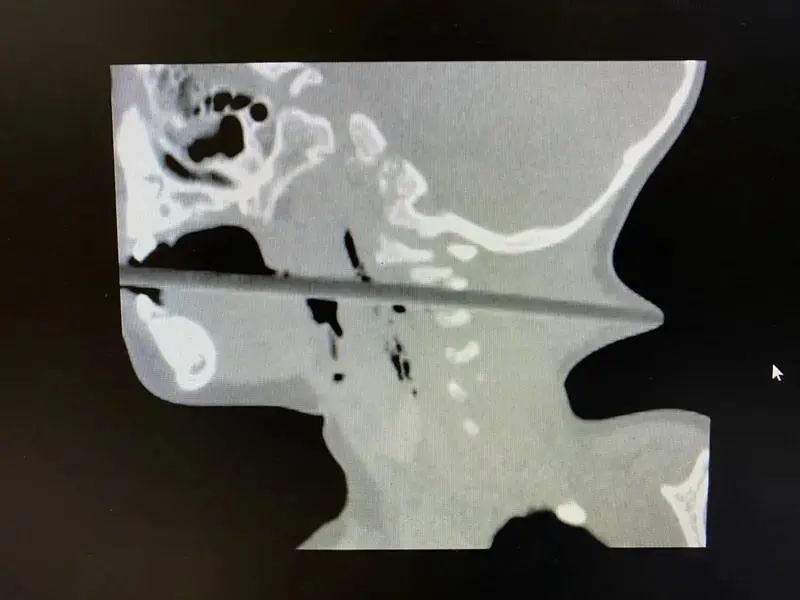

孩子被送往医院后,颈部CT结果显示:二十多厘米的筷子从患儿的口腔进入,经过咽部后壁,通过颈椎2、3间隙,一直向后到达后颈,几乎戳穿了皮肤。

南京市儿童医院神经外科主治医师邱德智说:“虽然筷子没有伤到患儿的食道和气管,但可能损伤椎动脉和颈神经,术中很有可能造成大出血危及生命。”还好,最终手术成功将筷子从林林的口中取出,孩子脱离了危险。